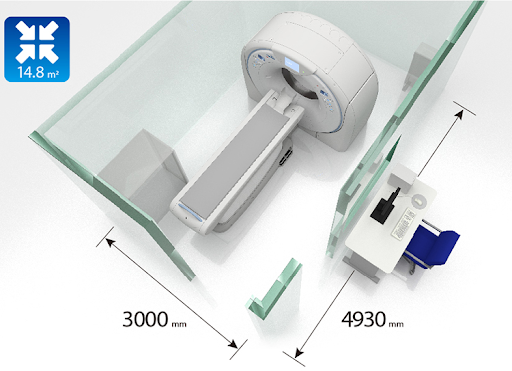

Aquilion Prime SP - это правильный выбор для любого диагностического отделения. Aquilion Prime SP обеспечивает высокую производительность, безопасность для пациентов, а также платформу для расширения портфеля изображений для повышения производительности.

Aquilion Prime SP - это правильный выбор для любого диагностического отделения. Aquilion Prime SP обеспечивает высокую производительность, безопасность для пациентов, а также платформу для расширения портфеля изображений для повышения производительности.